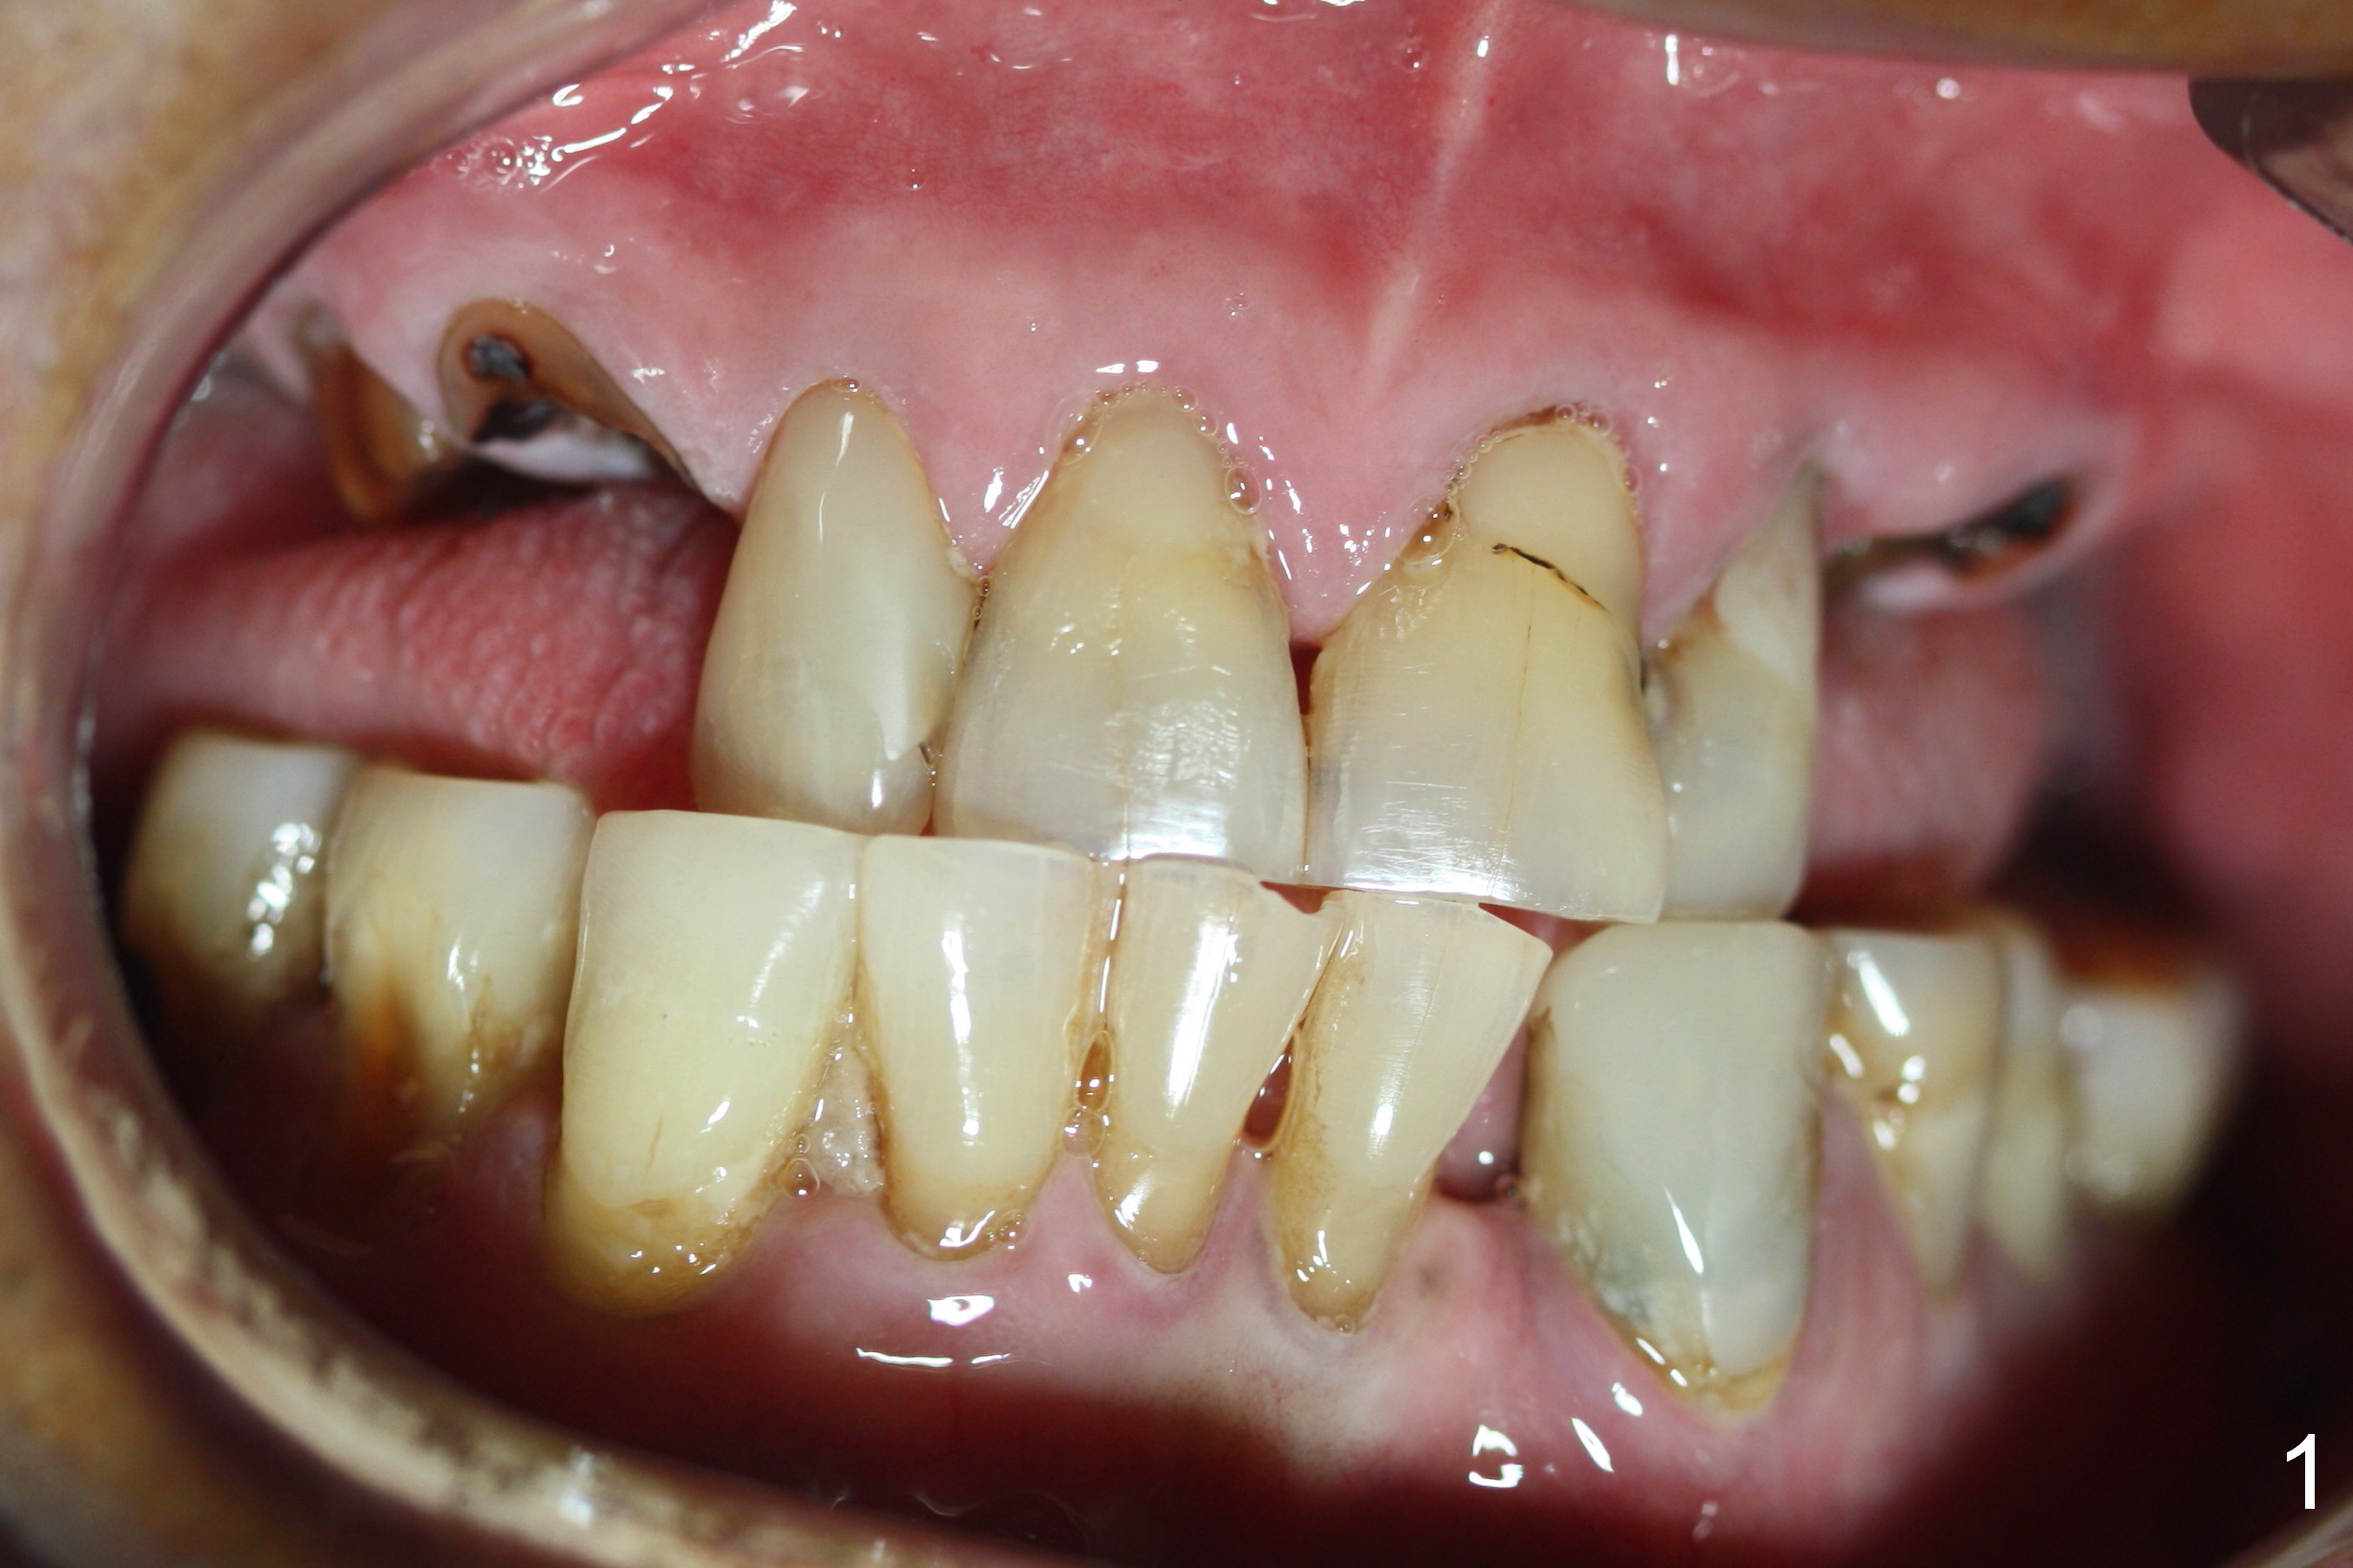

Several of CK's upper teeth (apparently in cross bite) are to be restored with implants (Fig.1). The first two are #5 and 6; note the oval roots (Fig.2). After extraction, and curettage, osteotomy starts in the palatal aspect of each socket. The 1st intraop PA shows that the trajectory at #6 is incorrect (Fig.3). After adjustment, osteotomies look parallel (Fig.4: D: 3.5x20 mm drill; T: 4.5x20 mm tap). This suggests how important it is to use parallel pins to check initial osteotomies for neighboring implants (Fig.3). The trajectory of the implants remains acceptable (Fig.5: 4.5x20 mm with insertion torque »60 Ncm); so is the position of the implants (as palatal as possible; Fig.6 (*: bone graft)). Immediate provisionals are fabricated in cross bite.